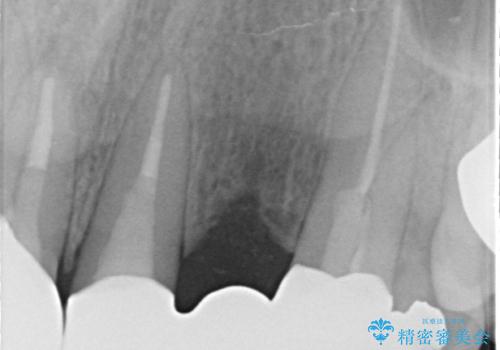

- 昔入れた被せ物と歯茎の間の隙間が気になると来院された方の症例です。

右上1、2番目の歯と左上1、2、3、番目の歯のブリッジを除去し、オールセラミッククラウンによる補綴を行うことで見た目を改善しました。

今回用いたオールセラミッククラウンはジルコニアフレームという白い素材の上にセラミックを盛っているため、審美性が非常に高いのが特徴です。

また、ジルコニアは人工ダイヤモンドの材料にも使われているほど高い強度を持っており、そのためオールセラミッククラウンは審美性だけでなく、奥歯やブリッジの補綴も可能とするクラウンです。